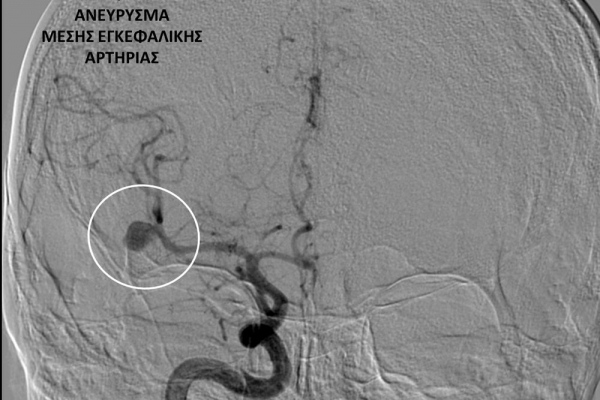

- Η ψηφιακή αγγειογραφία (DSA) αποτελεί την καλύτερη μέθοδο διάγνωσης των αγγειακών παθήσεων.Η αγγειογραφία γίνεται ως εξής: αρχικά παρακεντάται μια αρτηρία πρόσβασης, όπως η μηριαία αρτηρία στη βουβωνική περιοχή ή η βραχιόνια αρτηρία στο βραχίονα. Στη συνέχια προωθείται ένας καθετήρας προς την περιοχή του ενδιαφέροντος και γίνεται η έγχυση σκιαγραφικής ουσίας (σκιαγραφικού) με συνεχή λήψη «εικόνων» των αγγείων-στόχων.